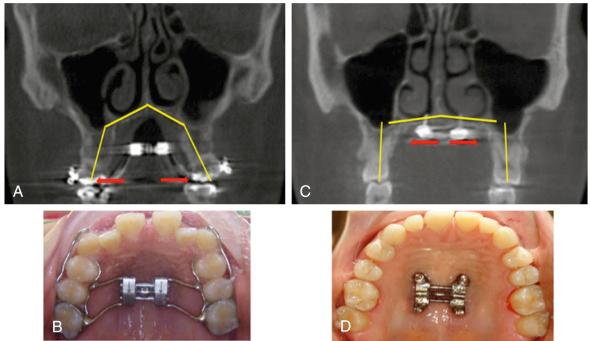

The combination of minimally invasive surgery and bone-anchored expanders takes full advantage of the principles of distraction osteogenesis (DO) and reliably expands the maxilla in adults with OSA and narrow, high, arched palatal vaults ( Fig. 59.1 ).

FIG. 59.1, Comparison of tooth- versus bone-anchored expanders.